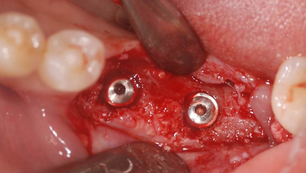

The staged approach on atrohpic ridge using NeoBiotech IS II active fixture and nonresorbable membra

Situation Patient Information Female 60 yrs old Non-contributory NKDA Drink occasionally, never smoked PDH Extraction #36,37,46 Scaling...

Dr. Seok Yong Kim

Nov 13, 20152 min read